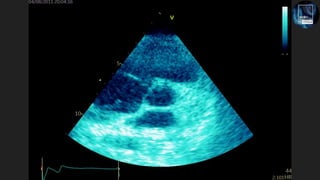

The document discusses the potential of echocardiography in managing cardiac arrest, emphasizing its non-invasive and painless nature for bedside assessments. It highlights the importance of recognizing the causes of cardiac arrest, such as hypovolaemia and tension pneumothorax, and the need for proper training of healthcare staff. Additionally, it provides resources for further learning, including social media and a dedicated website.